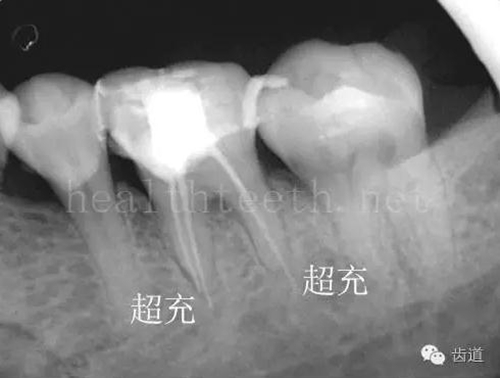

不良的根管充填治療

77.jpg

78.jpg

79.jpg